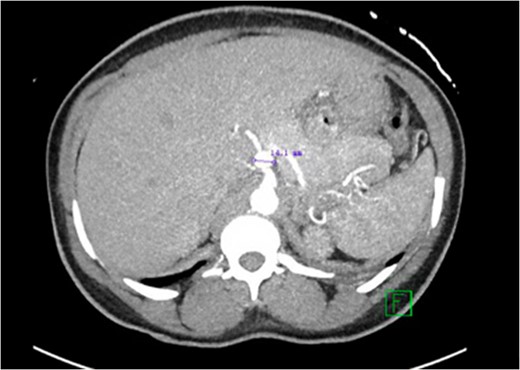

CT abdomen with contrast demonstrating the location and size of the aneurysm.